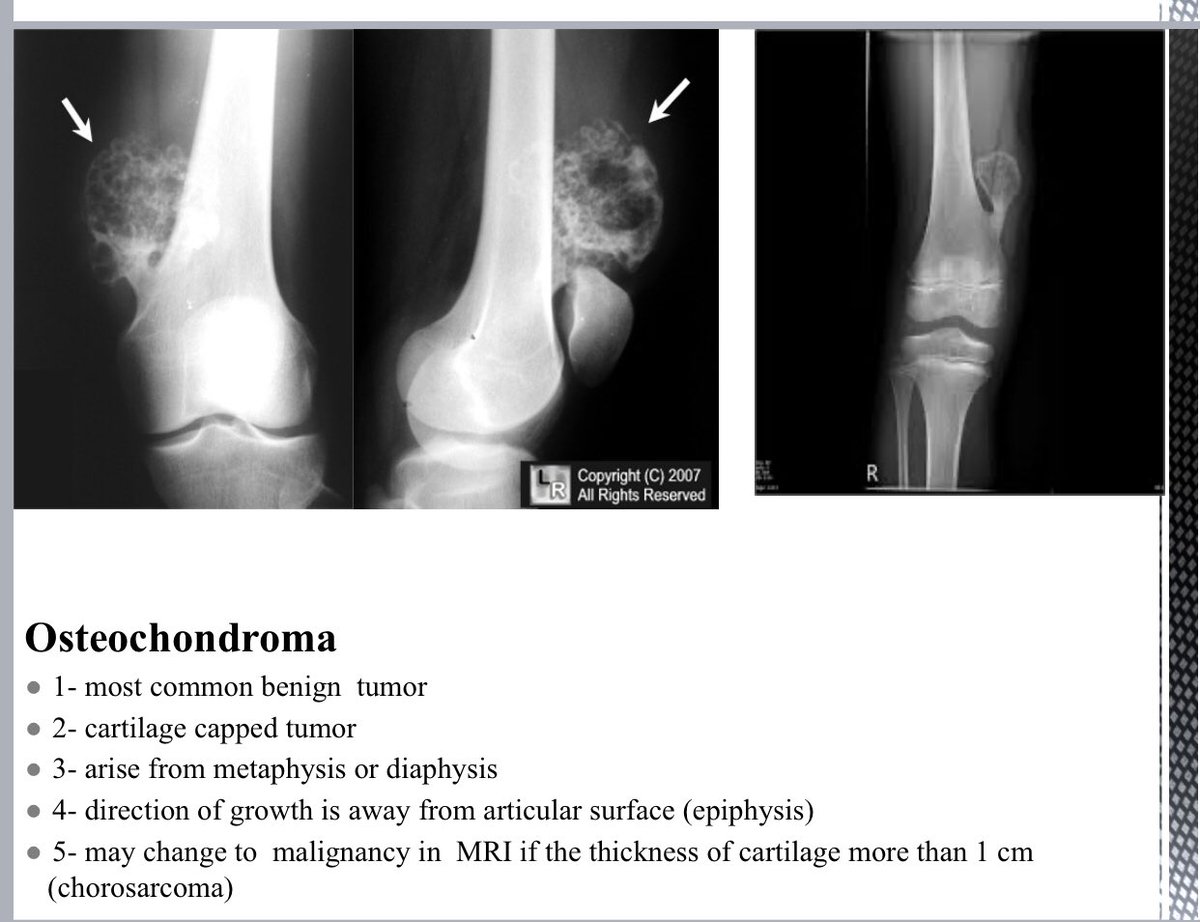

ثريد اليوم مليء بالمعرفة ومهم جداً لـ Skeletal System وأبرز الامراض مع شرحها بشكل مختصر بالصورة والمرض وأبرز العلامات الي من خلالها نحدد نوع Diagnosis راح تفيدكم بشكل كبير سواءً للطلاب أو الموظفين أو الأطباء .